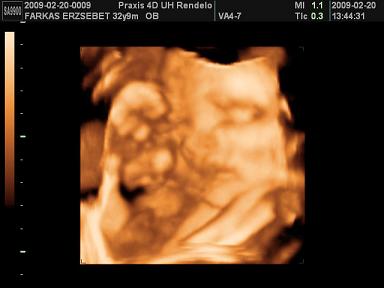

Megjöttünk 4D-ről, még mindig Iringó! :-) Az összes keze lába meg még a köldökzsinór is az arca előtt volt, de a dokinő addig ügyeskedett, míg csak sikerült értelmes képet kapni.

Novygirl, mi is a Praxisban voltunk, percre pontosan fogadtak, én Hajdú Krisztinánál voltam, normális volt. Regisztráltam előtte itt a babaneten én is. Hátul parkoltam a buszmegállónál és mivel utána a férjem még ment vissza melózni, így beültünk ott egy kávézóba kicsit és volt gyereksarok, Gyöngy játszott, még pelenkázó helyiség is volt, nagyon szimpatikus hely! Igaz, nem olcsó, egy kávé és egy cola 900 Ft, de egyszer ki lehet bírni.

Kép Iringó